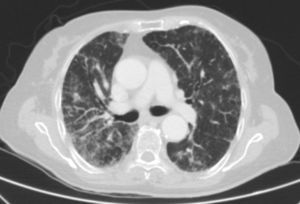

Caso clínicoSe trata de una mujer de 83 años, con antecedentes de hipertensión arterial en tratamiento con amlodipino 5mg/día, enfermedad renal crónica en estadio iii, secundario a nefroangioesclerosis (filtrado glomerular de 45ml/min) y polimialgia reumática en tratamiento crónico con metotrexato 15mg/semanal, desde hace 4 años, aproximadamente. Durante los últimos años ha permanecido con buena estabilidad clínica y analítica, no requiriendo tratamiento corticoideo asociado ni ajustes de su medicación habitual. Seis semanas previas al ingreso presentó de forma progresiva astenia, disnea, tos productiva y pérdida ponderal de 5 kg durante este tiempo. No fiebre termometrada, no artralgias ni debilidad muscular. En el ingreso, se objetivó disnea en reposo con saturación de oxigeno basal del 90%, auscultación pulmonar con crepitantes finos bilaterales, no adenomegalias ni visceromegalias palpables, elevación de la velocidad de sedimentación globular de 69mm, proteína C reactiva de 3,5mg/dl y radiografía de tórax, donde destacó un infiltrado reticular bilateral difuso y asimétrico con afectación periférica, más acentuado en las bases y en el lóbulo superior derecho (fig. 1). Tras realizar un diagnóstico diferencial de neumopatía subaguda en el contexto de la paciente, la sospecha de neumopatía por metotrexato fue el principal planteamiento, por lo que se suspendió dicho tratamiento, se inició corticoterapia por vía intravenosa de 48mg/día de metilprednisolona y medidas de soporte, a pesar de lo cual no se objetivó clara mejoría. Se realizó una tomografía axial computarizada de alta resolución (TACAR) torácico, objetivándose un engrosamiento intersticial parcheado de predominio periférico y en las bases pulmonares, así como pequeñas adenopatías mediastínicas inespecíficas (fig. 2). Las pruebas de función respiratoria mostraron una espirometría forzada con valores en el límite bajo de la normalidad, con una capacidad vital forzada (FVC) de 1.340ml (82%), un volumen de flujo espiratorio en el primer segundo (FEV1) de 1.130ml (88%) y el cociente FEV1/FVC del 84%, asociado a un descenso grave de la difusión pulmonar de monóxido de carbono (DLCO) del 33% y corregido según el volumen alveolar (KCO) del 54%. En el resto de las pruebas complementarias, no se evidenciaron alteraciones en el hemograma, la serología para gérmenes atípicos, el estudio de marcadores tumorales, los hemocultivos, el estudio seriado de esputo ni en el Mantoux/Booster, por lo que se realizó una broncoscopia con estudio del lavado broncoalveolar (LBA) y broncoaspirado, obteniéndose resultado positivo en la reacción en cadena de la polimerasa (PCR) para CMV asociado a un incremento del índice de linfocitos CD4/CD8 de 3.47, con el resto de estudio para gérmenes comunes, tuberculosis, Pneumocistis jiroveci y hongos negativo. Se amplió el estudio microbiológico detectándose IgG para CMV (+), IgM para CMV (–) y carga viral CMV en plasma (+), por lo que se inició tratamiento por vía intravenoso, ajustado según función renal, con ganciclovir 300mg/12 h durante 14 días, cambiando posteriormente a valganciclovir 900mg/12 h por vía oral durante 14 días, con buena tolerancia a la medicación y respuesta clínica, mejorando los parámetros radiológicos, serológicos (carga viral CMV indetectable) y de función respiratoria (DLCO 57,52%, KCO 80,90%, FVC 1.950ml [119%] y FEV1 de 1.680ml [130%]).